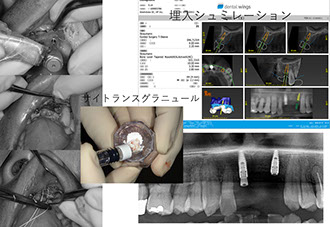

インプラント治療39年

当院のインプラント治療はデジタルCTデータを基に専用ソフトにてインプラント手術をシミュレーションし、手術から最終補綴まで安心、安全そして長期安定性を目指し最新のプロトコルによるデジタルシステムで対応しています。また、骨の状態により骨増生、サイナスリフト、ソケットリフト、ボーンスプレッディング等、様々な対応をいたします。

様々なデジタル機器を導入し治療精度の向上に努めています